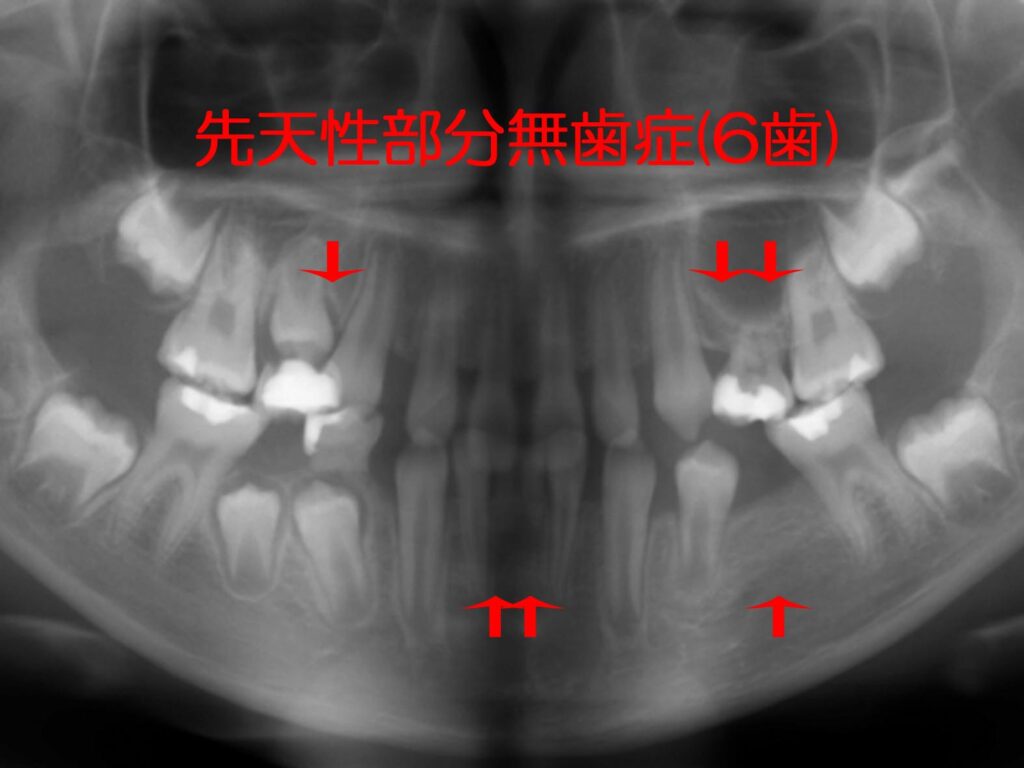

下顎多数歯欠損インプラント症例|症例解説|東京銀座シンタニ, 多数歯先欠・6歯以上の先天性部分無歯症の矯正治療,

多数歯先欠・6歯以上の先天性部分無歯症の矯正治療, 多数歯欠損ケース治療実績|実績・症例|朝霧 インプラント【書籍概要】本書は、インプラント治療に関する専門的な知識を提供することを目的とした書籍です。特に多数歯欠損や無歯顎症例に焦点を当て、実践的な治療法や症例を詳述しています。【著者情報】著者は、インプラント治療の分野で豊富な経験を持つ専門家たちで構成されています。彼らの知識と技術が詰まった一冊です。【対象読者】この書籍は、歯科医師や医療従事者、インプラント治療に関心のある方々に最適です。専門的な内容が多く含まれているため、実務に役立つ情報が得られます。- タイトル: MAXILLA-ORIENTED IMPLANTOLOGY- 著者: 林 裕幸, 武田 幸之, 桜井 幸弥, 森田 謙治- 出版社: ゼニス出版- 言語: 日本語- テーマ: 多数歯欠損・無歯顎症例のインプラント治療ご覧いただきありがとうございます。

多数歯欠損ケース治療実績|実績・症例|朝霧 インプラント【書籍概要】本書は、インプラント治療に関する専門的な知識を提供することを目的とした書籍です。特に多数歯欠損や無歯顎症例に焦点を当て、実践的な治療法や症例を詳述しています。【著者情報】著者は、インプラント治療の分野で豊富な経験を持つ専門家たちで構成されています。彼らの知識と技術が詰まった一冊です。【対象読者】この書籍は、歯科医師や医療従事者、インプラント治療に関心のある方々に最適です。専門的な内容が多く含まれているため、実務に役立つ情報が得られます。- タイトル: MAXILLA-ORIENTED IMPLANTOLOGY- 著者: 林 裕幸, 武田 幸之, 桜井 幸弥, 森田 謙治- 出版社: ゼニス出版- 言語: 日本語- テーマ: 多数歯欠損・無歯顎症例のインプラント治療ご覧いただきありがとうございます。